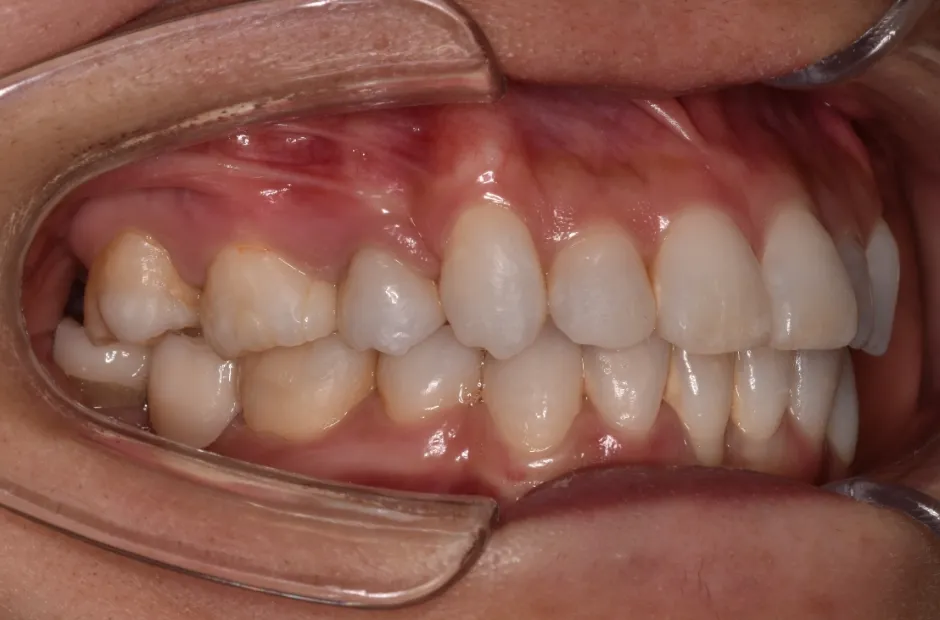

叢生

| 診断名・主訴 | 叢生 |

|---|---|

| 年齢・性別 | 43歳・女性 |

| 治療期間・回数 | 2年7か月 27回 |

| 治療に用いた主な装置 | 舌側矯正 |

| 抜歯部位 | 両顎4,4 |

| 治療費 | 100万円(税抜) |

| リスク・副作用 | 装置による違和感・疼痛・歯肉退縮・歯根吸収・虫歯のリスクなど |

治療前

治療中

治療後